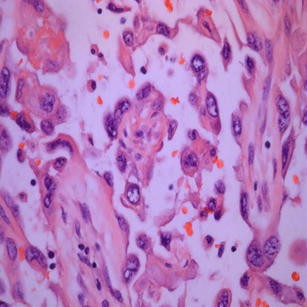

Fig. 4